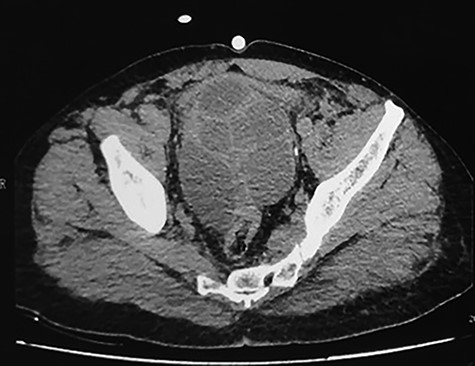

A 59-year-old patient presented at the emergency department with an acute urine retention. As a past medical history, the patient suffered from chronic hypogastric pain with LUTS and constipation over a period of 6 months. The clinical examination revealed a distended bladder that required transurethral bladder catheterization. The digital-rectal examination showed a bulging pelvic mass in the rectum, the prostate has not been palpated. The blood analysis revealed an elevation of creatinine level to 123 μmol/l with hyperleukocytosis. Prostate-specific antigen (PSA) was within normal range and urine culture was negative. Abdominal and pelvic Computed tomography (CT) scan was performed and showed a multilocular heterogeneous cystic mass in the rectovesical and supravesical spaces, measuring 13 × 10 × 9 cm, compressing the bladder and the two ureters with bilateral major upper tract dilation. The cystic mass had many septa of different thickness mildly enhancing after contrast administration (Fig. 1). There were no nodular solid enhancing components or evident signs of lymphadenopathies or metastatic lesions.

CT scan showing pelvic multilocular heterogeneous cystic mass with many septum mildly enhancing after contrast.